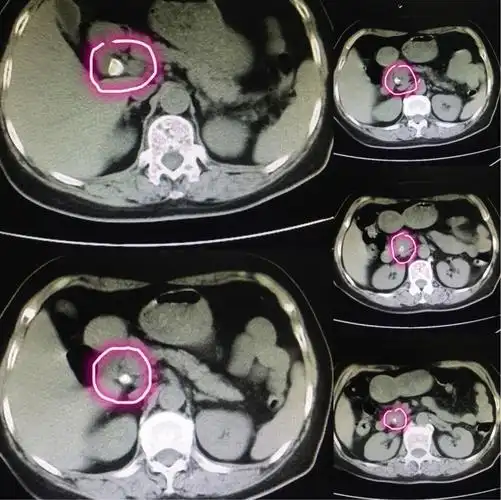

急腹症影像:胆道结石ct表现!

ct横断面可见结石自下而上填满胆总管.

56岁,胆总管结石并急性胆囊炎,胆管炎急诊入院,经ct检查证实为:胆石症